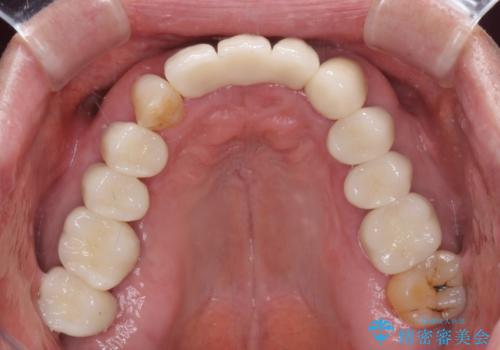

- 上の前歯が痛むとのことで来院された患者様です。

検査を行ったところ、前歯1本は周辺の骨が失われており、抜歯が必要でした。

上顎の奥歯は全体的に歯周ポケットが散見され出血が認められたため、歯周外科処置を行うこととしました。

上の歯は見た目を良くしたいというご希望があったため、歯周外科処置を行った歯についてはセラミッククラウンで補綴することとしました。